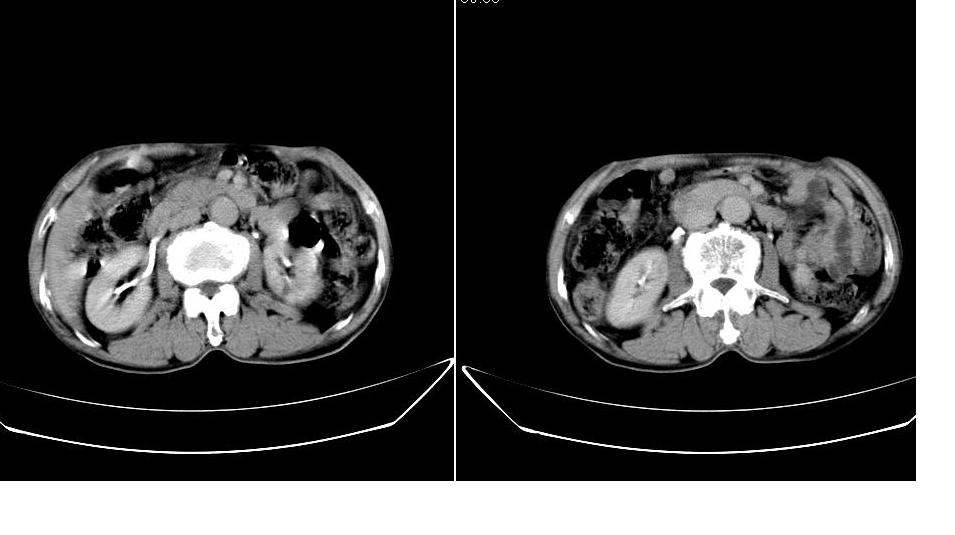

男,76岁,上腹部疼二天来就诊,彩超提示肝左叶占位,随后做上腹部ct平扫,今天做上腹部ct增强扫描,手工推药,效果不好,请谅解。

肝左叶s4肿块强化形式大概是:慢进慢出,逐渐强化----考虑血管瘤/腺瘤?{动脉期应更提前扫}。

1)肝右叶前段低密度灶,不排除肝癌可能;建议查afp。2)右肾上极囊肿。

肝内胆管积气扩张,胆囊增大,肝右前叶低密度灶,逐渐强化,一元论,胆系感染,局限性肝脓肿;右肾囊肿。

考虑肝s4段肝脓肿可能?未排除肝癌。右肾上极囊肿。